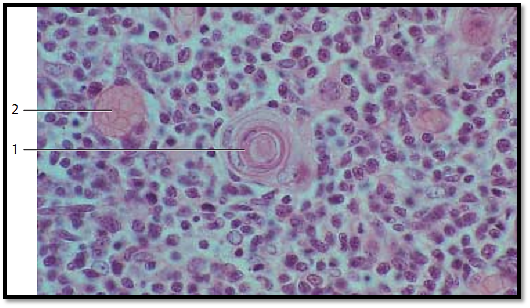

Thymus

Large Hassall corpuscle 1 in the medullary thymus from a child. The figure shows the concentric layering of the reticulum cells particularly well. Note the somewhat larger epithelial reticulum cells in the medulla which interconnect via their cell processes and form a meshwork . There are fewer lymphocytes in that area. The sectioned blood vessels 2 are filled with erythrocytes. The thymus is equipped with a blood-thymus barrier , which is restricted to the cortex.

1 Hassall corpuscle

2 Capillary

Stain: alum hematoxylin-eosin; magnification: × 400